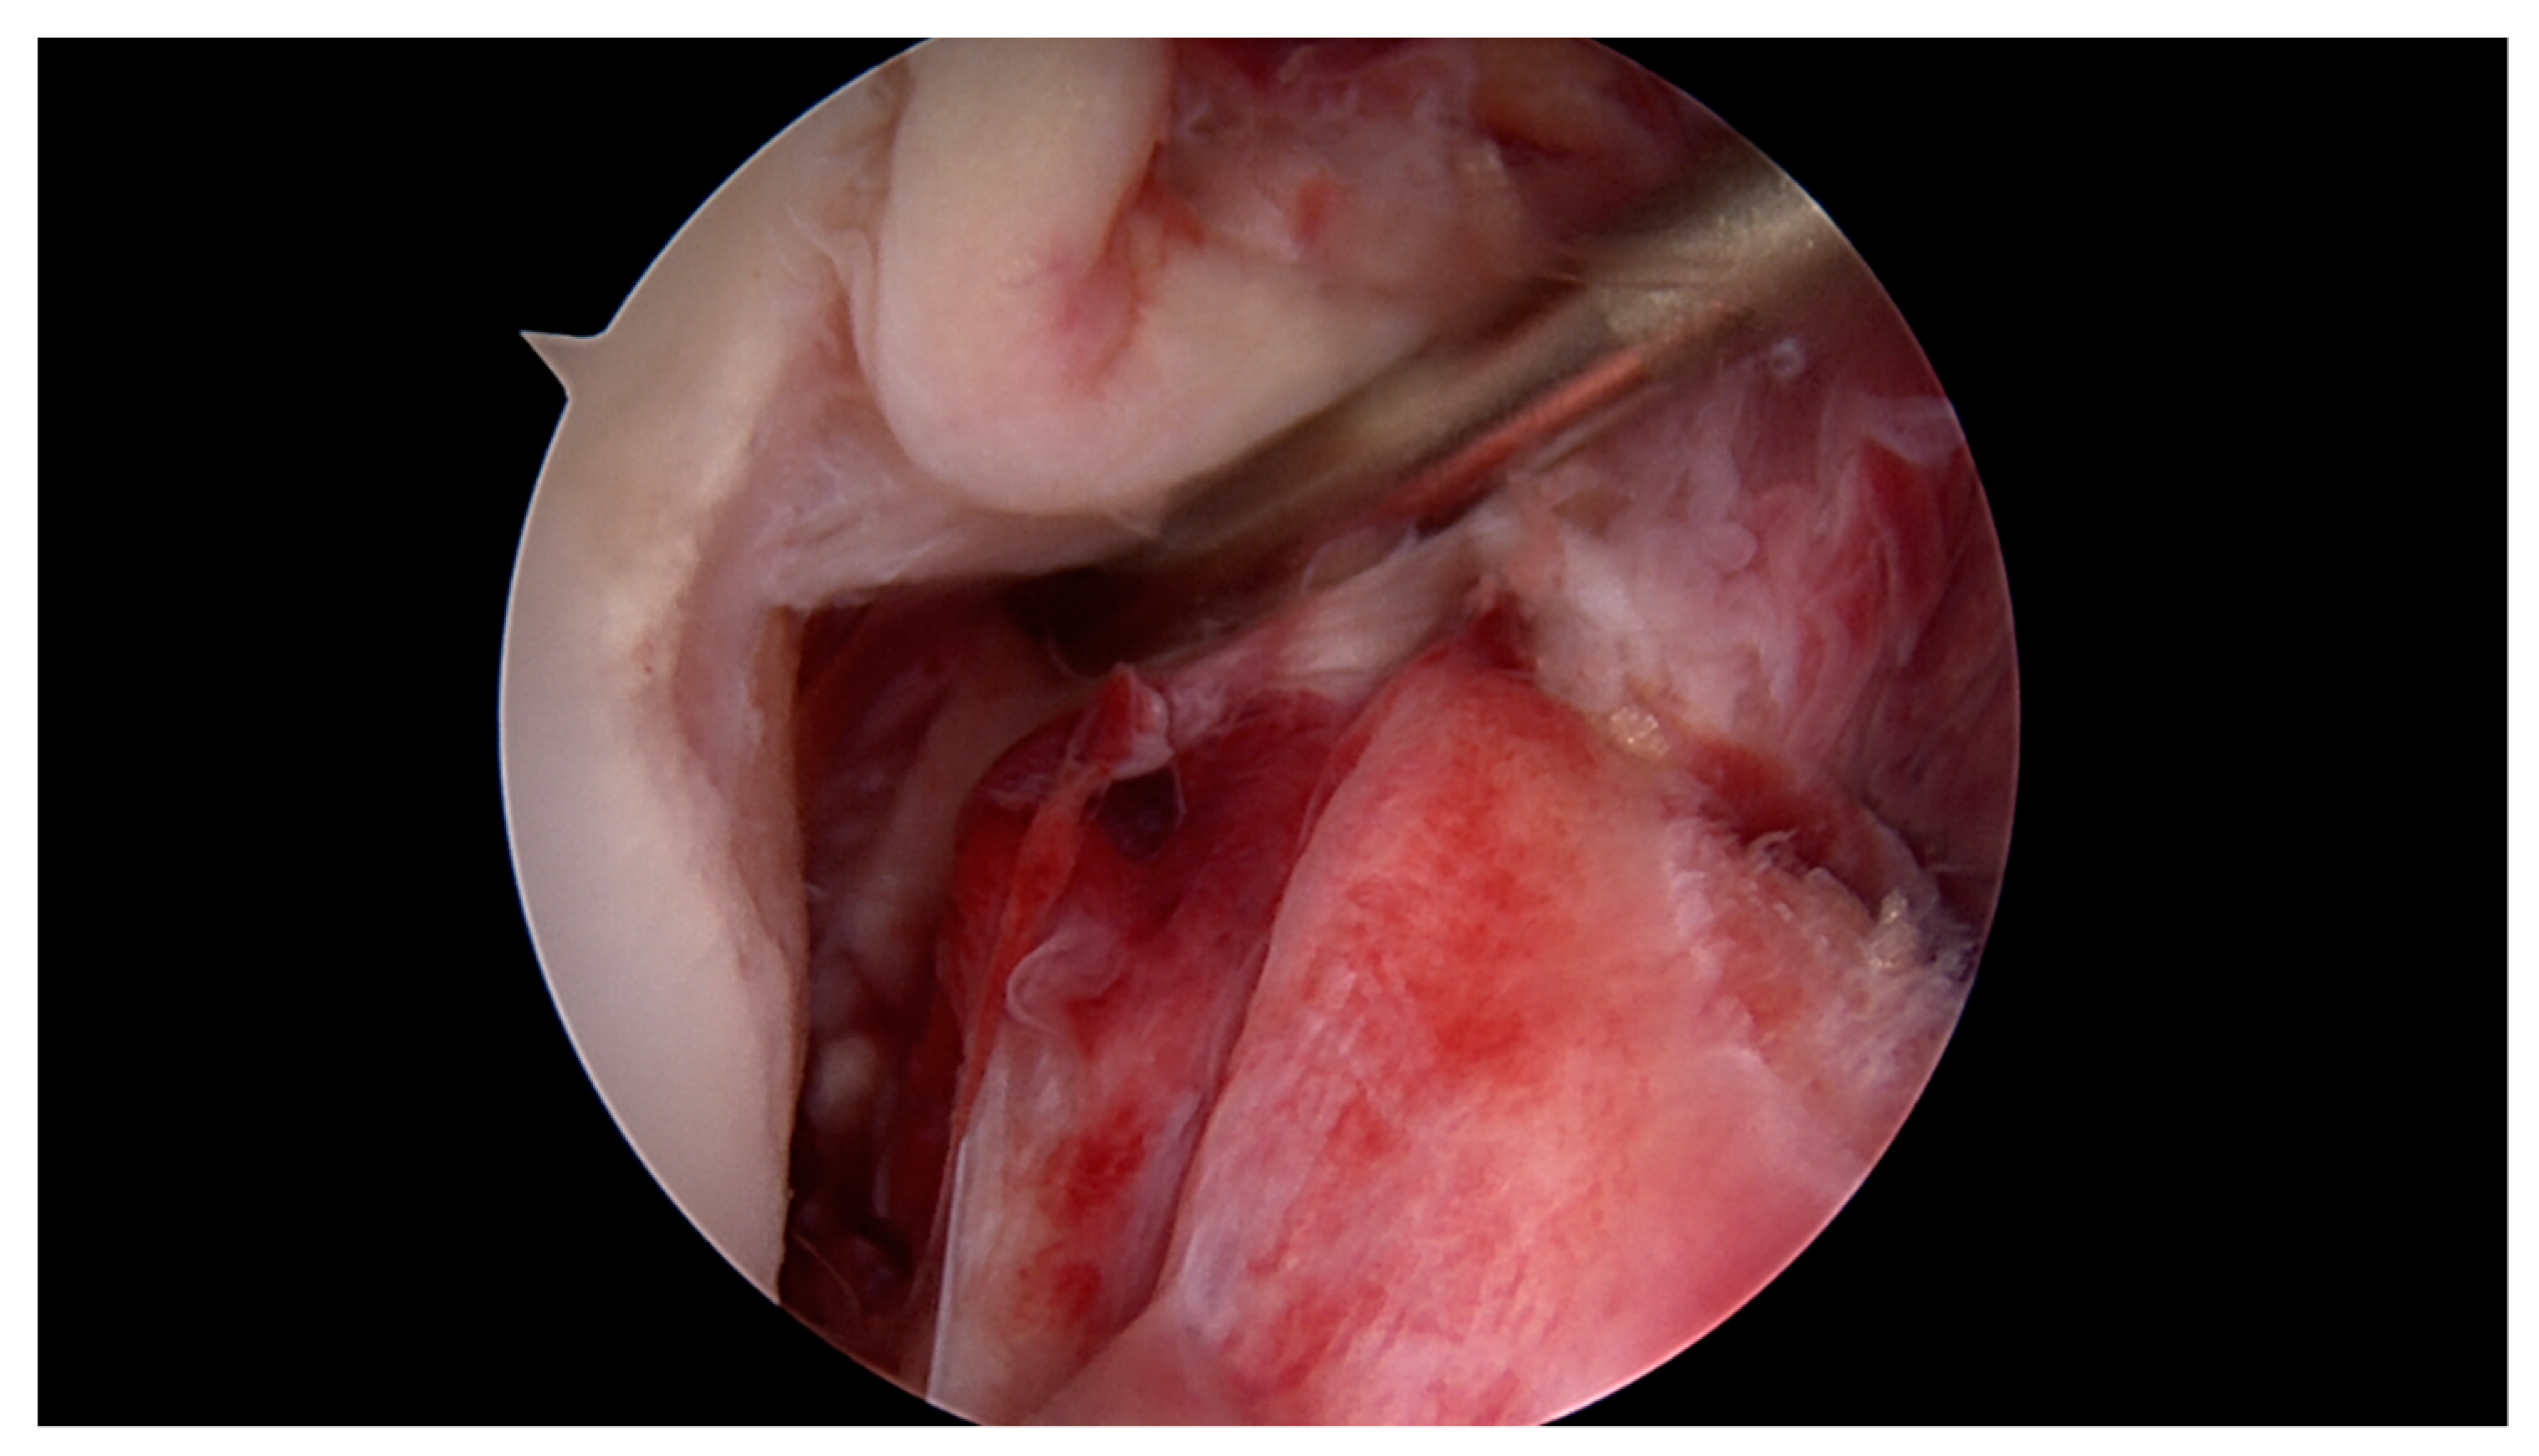

2.1. Surgical Technique and Rehabilitation